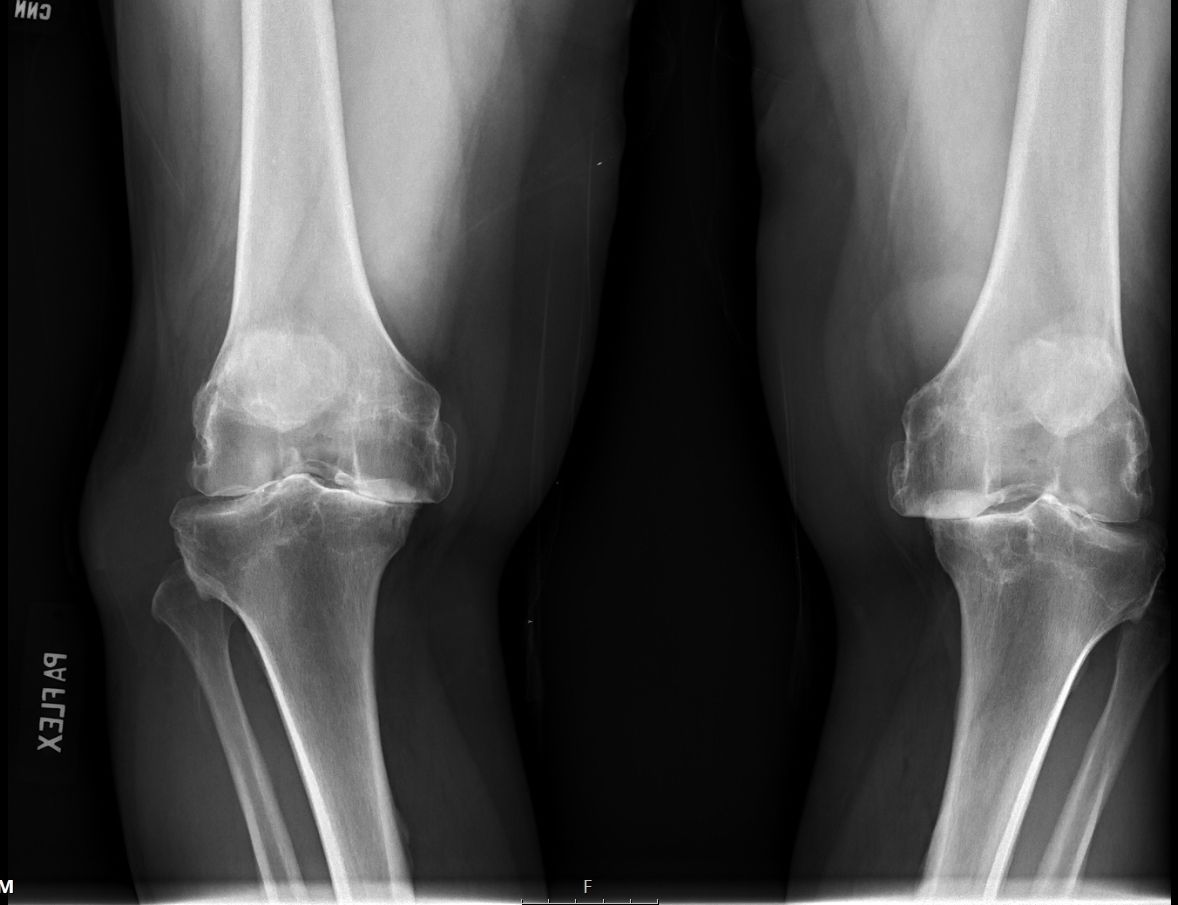

Joints Total Knee Arthroplasty (Cementless, Robotic-assisted) , and D. Gordon Allan , and James Lieber April 16, 2023